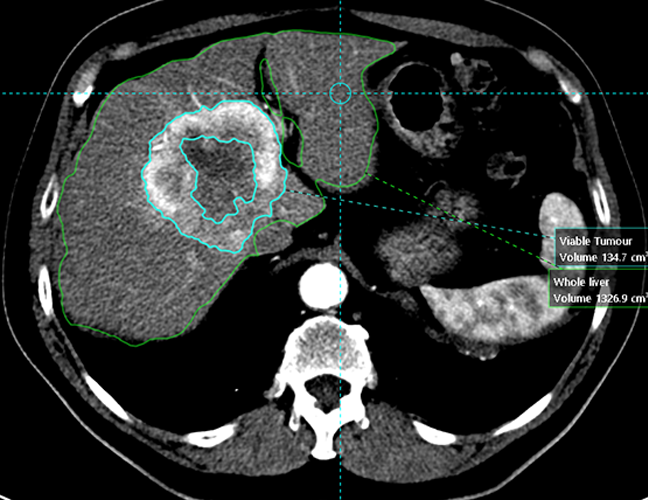

Simplicit90Y™ can be used to interactively tailor the absorbed dose per perfused volume by adjusting the injected activity. The software tools can be customised to a patient’s specific tumour presentation and anatomy.

Show heterogeneity of absorbed dose distribution in

critical structures, and assess tumour coverage